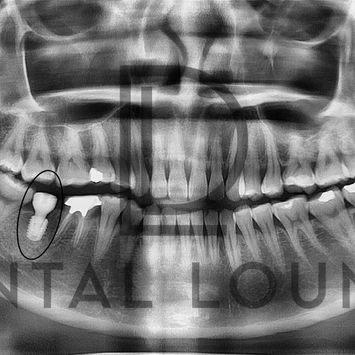

Post-operative Assessment

Post-op CBCT confirmed good implant angulation and position

IDN not involved

Megagen AnyOne Implant (5.0 × 7.0 mm) placed

Dentium healing abutment 6.5 mm (M) placed